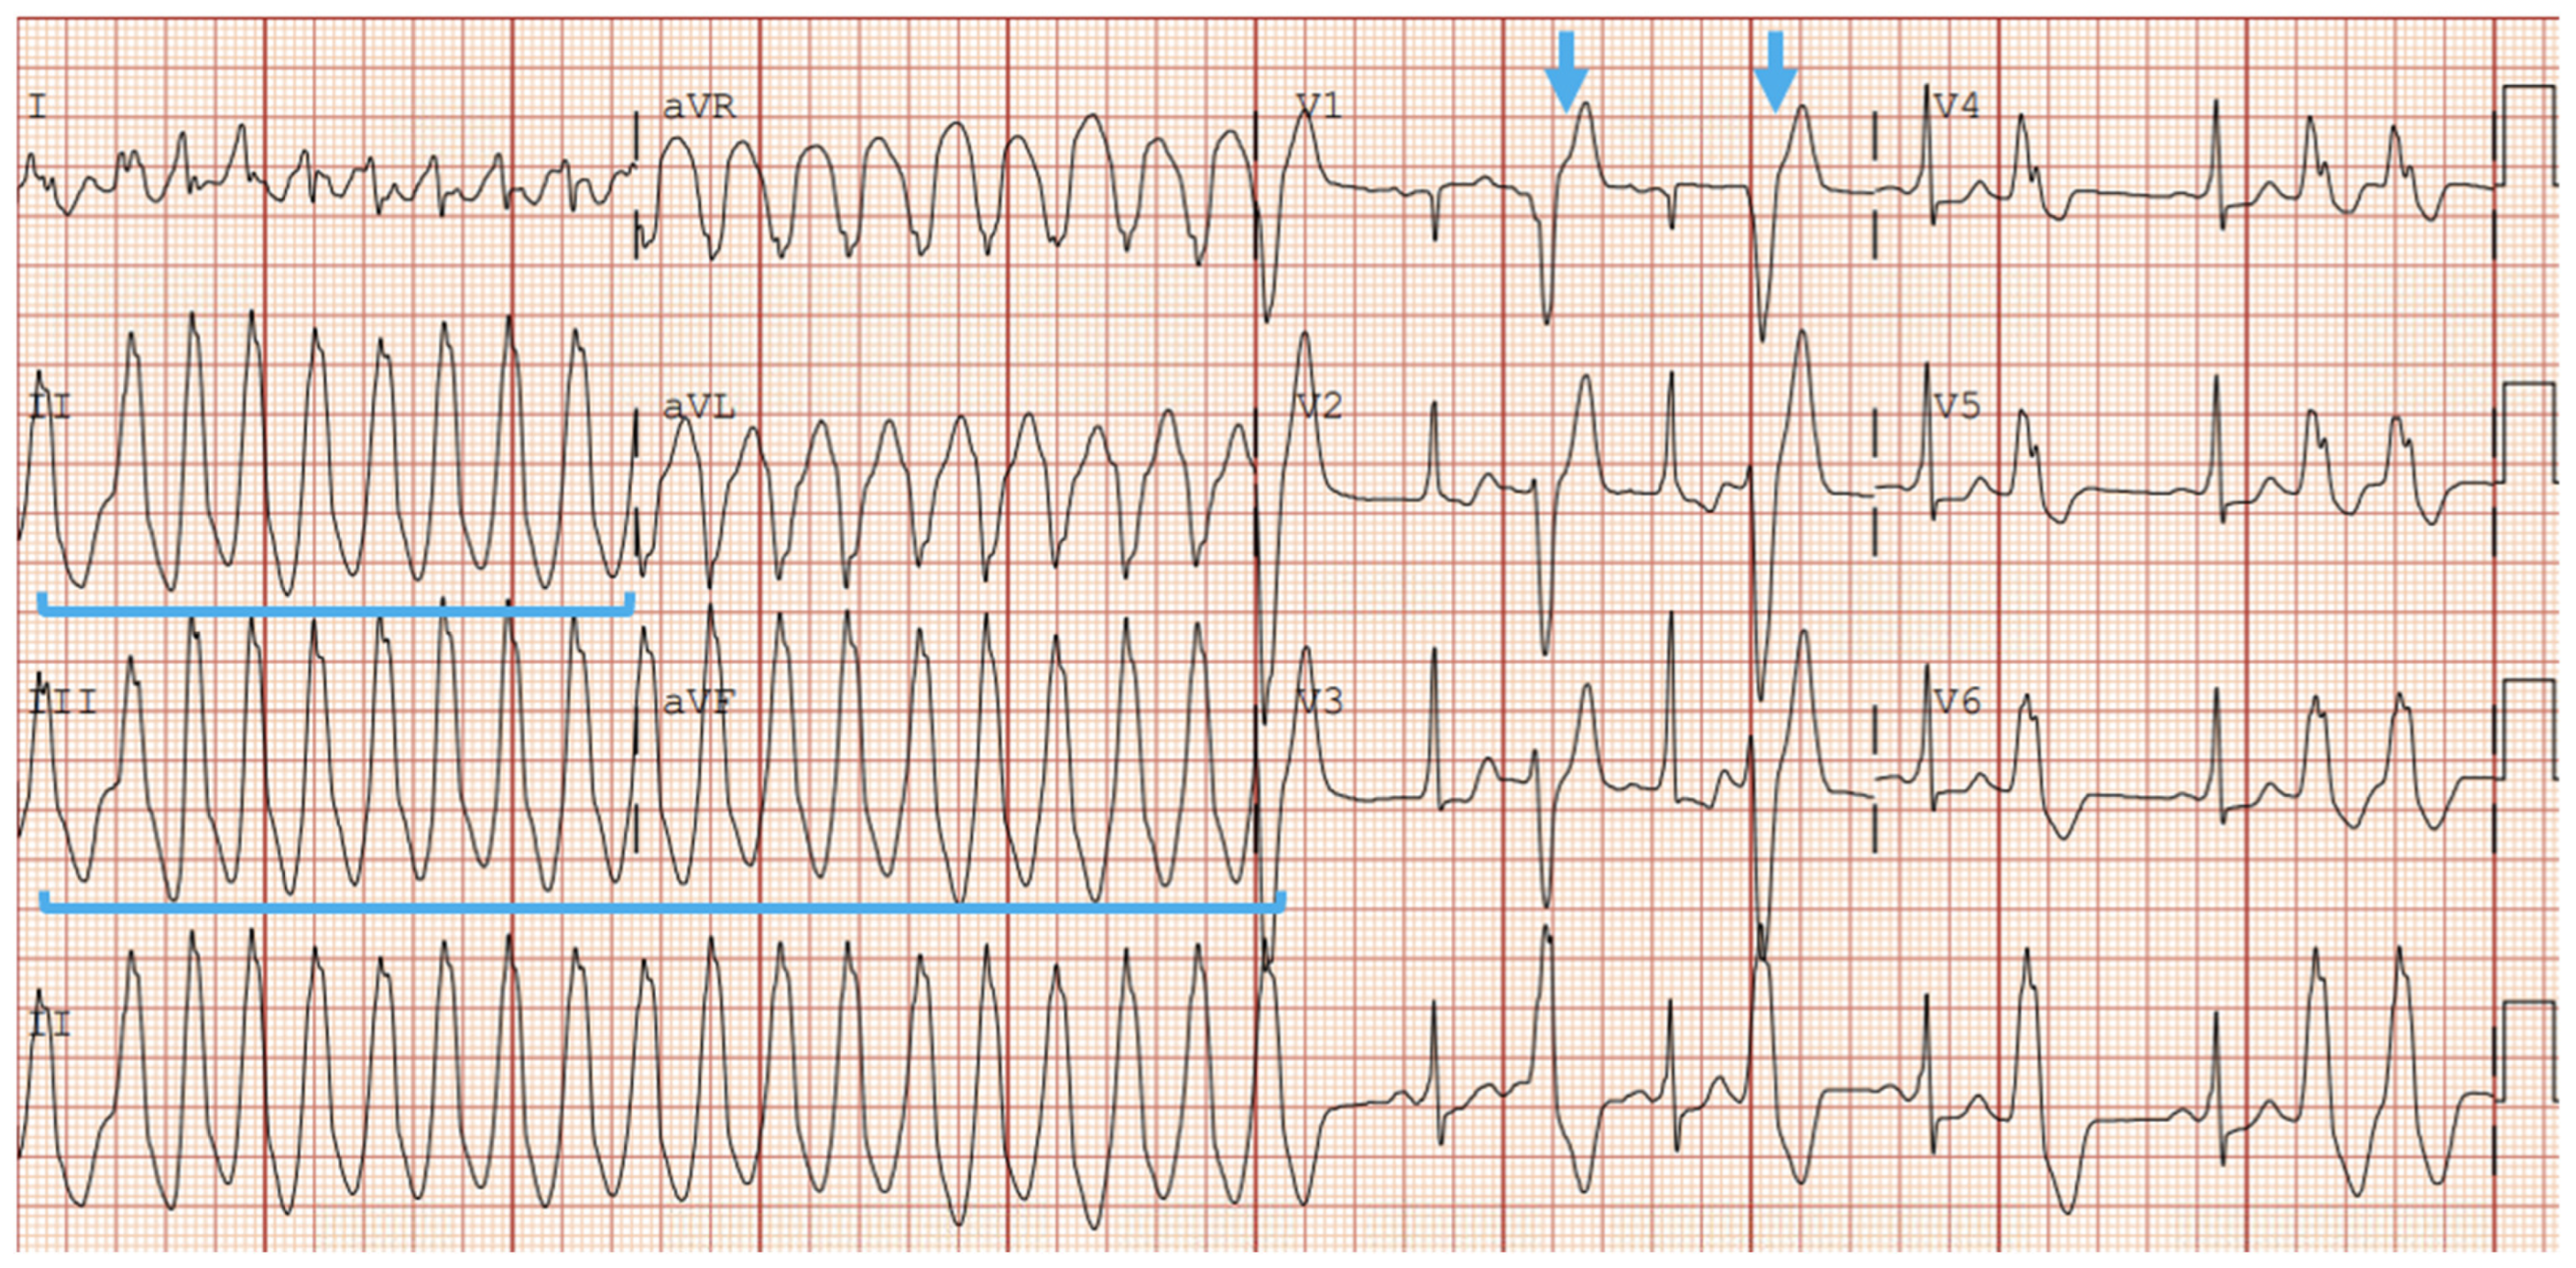

5.2.1. EKG and Holter Monitoring